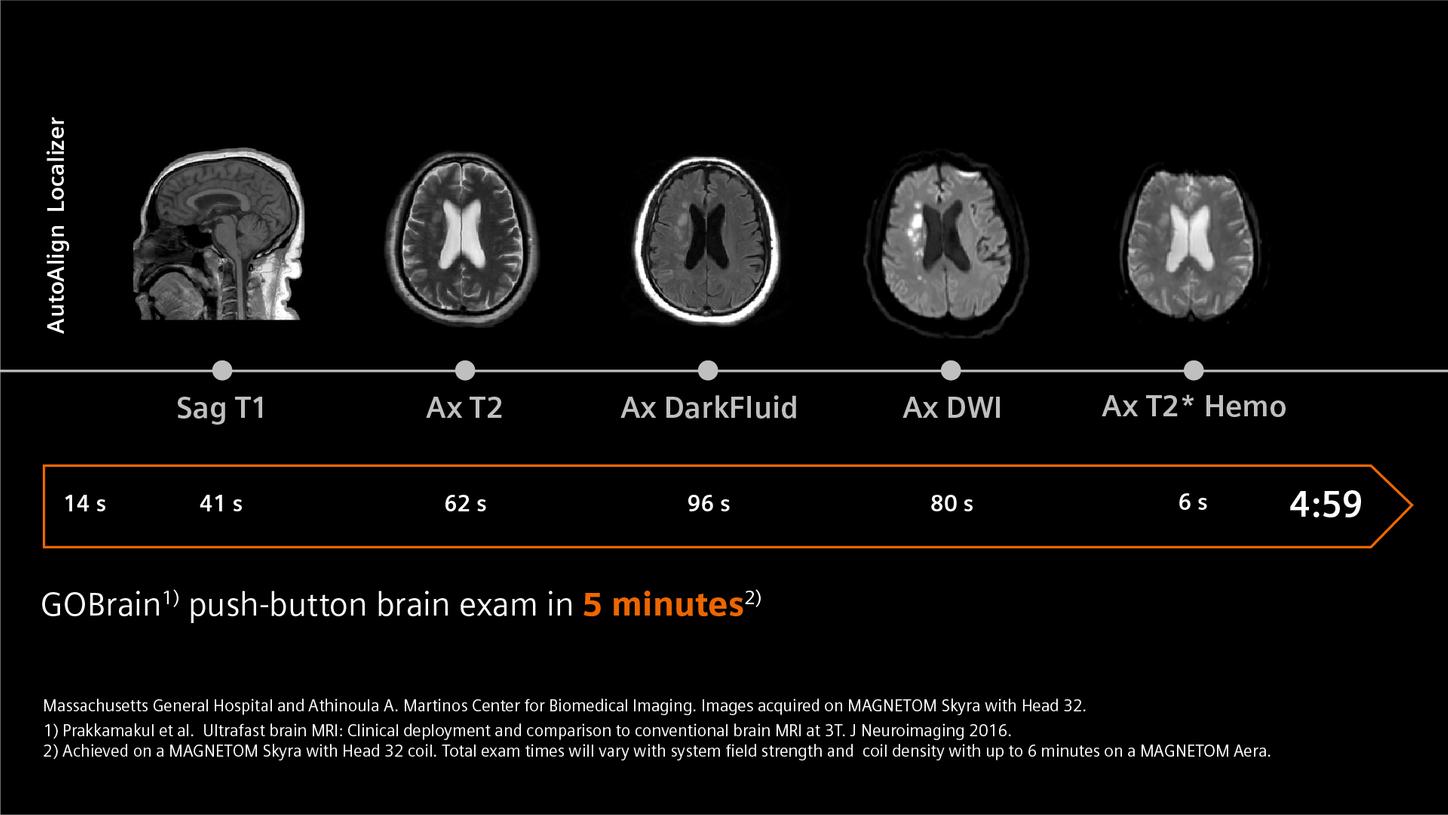

GOBrain1) allows push-button brain exams in 5 minutes2)

1) Prakkamakul et al. “Ultrafast brain MRI: Clinical deployment and comparison to conventional brain MRI at 3T.” J of Neuroimaging 2016

2) MAGNETOM Skyra, Head 32 coil. Exam times will vary.

GOBrain1) allows push-button brain exams in 5 minutes2)

1) Prakkamakul et al. “Ultrafast brain MRI: Clinical deployment and comparison to conventional brain MRI at 3T.” J of Neuroimaging 2016

2) MAGNETOM Skyra, Head 32 coil. Exam times will vary.